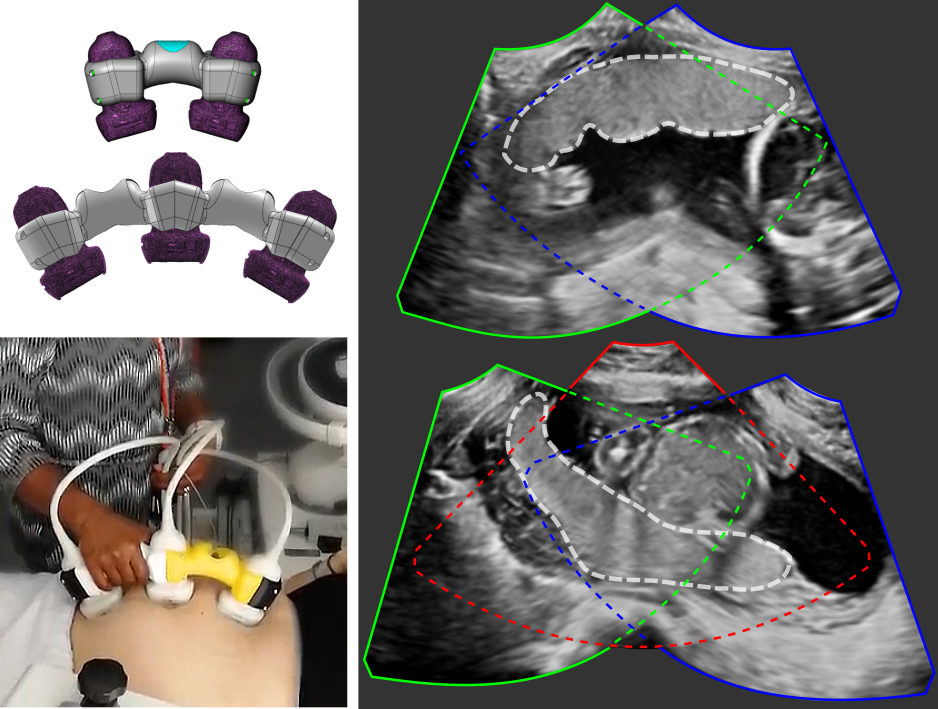

Multi-view placenta imaging with US requires two steps: (i) the image acquisition using multiple probes, and (ii) the multi-view image fusion, see Fig. 1 (b) for illustration.

Multi-probe ultrasound imaging. We acquire multiple US images using an in-house US signal multiplexer which allows to connect multiple Philips X6-1 probes to a Philips EPIQ V7 US system. The multiplexer switches rapidly between up to three probes so that images from each probe are acquired in a time-interleaved fashion. The manual movement speeds of the transducer array is within the Nyquist sampling rates. Therefore, for the purpose of data processing, consecutive images are assumed to have been acquired simultaneously over a small time window.

We designed a physical device that fixes the probes in an angle of 30∘ to each other, which ensures a large overlap between the images (see Fig. 1 (b)), and allows easy and comfortable operation. A.1 with Fig. 10 describe and show a more detailed illustration of the probe holder design with exact measurements.

Multi-view image fusion. We use a simple, but effective voxel-based weighted fusion strategy to suppress view-dependent artifacts in the images and extend the FoV. First, the images are aligned. This can be achieved via image registration, external tracking information, or fixed multiple probes, as described in the previous section. The weight of a (transformed) data point from each single image is formulated as a function of the depth in the US image with respect to the probe position and the beam angle. In effect, image points with a strong signal (to correct for shadow artifacts) and at a position close to the center of the US frustum (where the quality of the image is typically the best) will receive higher weights. The weighted fusion method is described in detail in Zimmer et al. (2018, 2019). We showed the potential of such acquired and constructed multi-view images for placental volumetry in Skelton et al. (2019).

When the spatial transformation between multiple images is known, e.g., by using a multi-probe system as described in Sec. 2 for image acquisition, the segmentations in individual images can be combined to obtain the segmentation in the multi-view image. The multi-view segmentation performance is reported in Table 3 and representative results are shown in Fig. 5.

Examplary multi-view images are shown in Fig. 5 with corresponding placenta segmentations with MTUNet and combined attention maps. The placenta is better visualized in the multi-view images with reduced image artifacts and an extended FoV. The multi-task model MTUNet provides an accurate segmentation and the combined attention maps localize well the placenta. Further examples of multi-view images with corresponding segmentations can be found in Fig. 12 in the appendix.